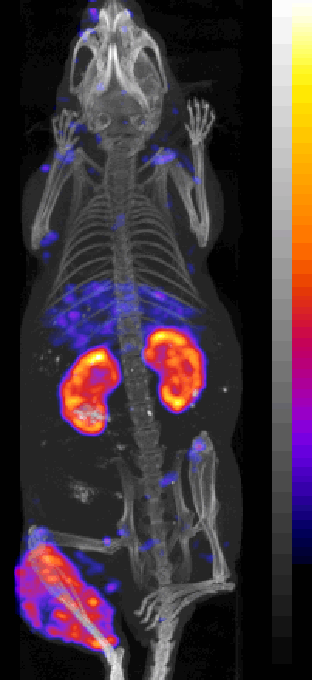

[18F]NaF Bone Scanning

188Re labeled oligomer |